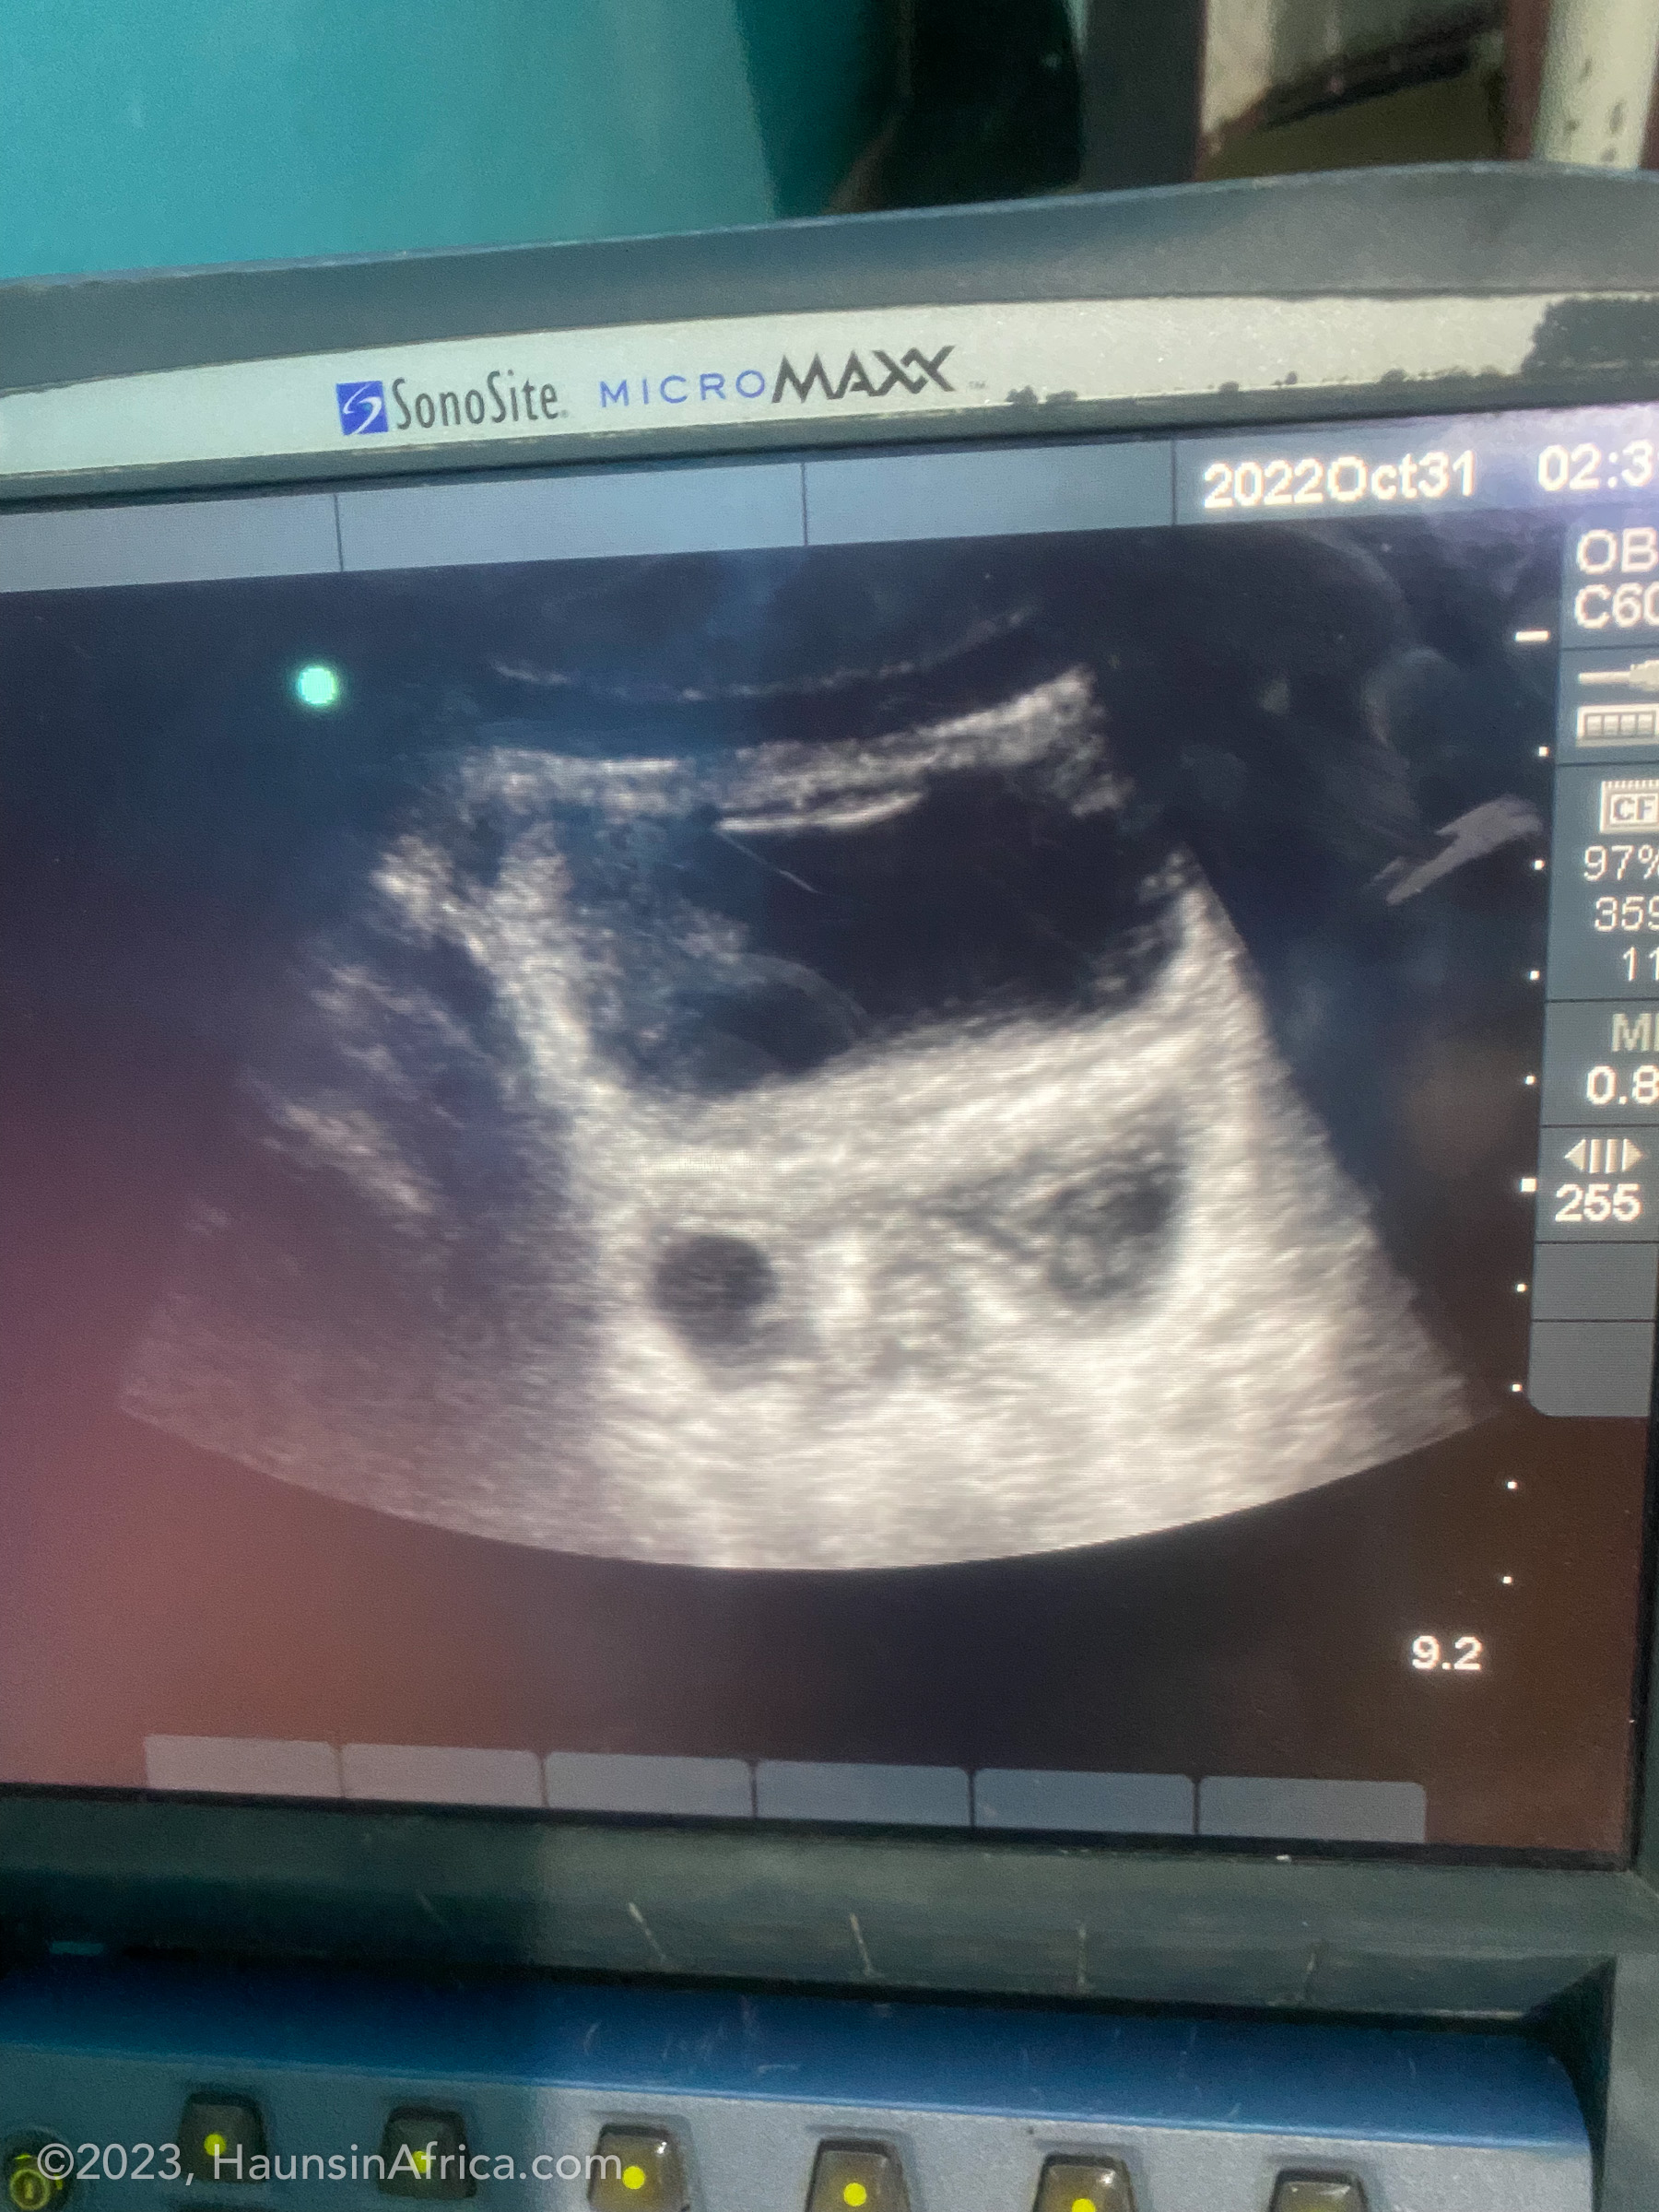

From haunsinafrica.com

Complications From a Ruptured Foley Balloon The Hauns in Africa Foley Balloon Complications There are some possible risks to having your doctor use a foley bulb. Foley balloon catheters have one of the best safety profiles with regard to uterine hyperstimulation and nicu admission 16, 17. The primary outcome was to determine the occurrence and rate of rupture with foley catheter balloon overinflation and any. This procedure does not require. In induction of. Foley Balloon Complications.

Complications From a Ruptured Foley Balloon The Hauns in Africa Foley Balloon Complications Here’s how the procedure works and what it feels like, plus a look at the benefits and potential risks. Foley balloon catheters have one of the best safety profiles with regard to uterine hyperstimulation and nicu admission 16, 17. Foley bulb is typically considered appropriate for folks who have had a previous cesarean birth. Inducing labor with a foley bulb. Foley Balloon Complications.

Complications From a Ruptured Foley Balloon The Hauns in Africa Foley Balloon Complications According to a 2018 systematic review, the risks of using a foley bulb to dilate the cervix are low. There are some possible risks to having your doctor use a foley bulb. Inducing labor with a foley bulb or foley balloon is a safe, simple method that can be a good choice for women who’d like to try avoiding induction. Foley Balloon Complications.